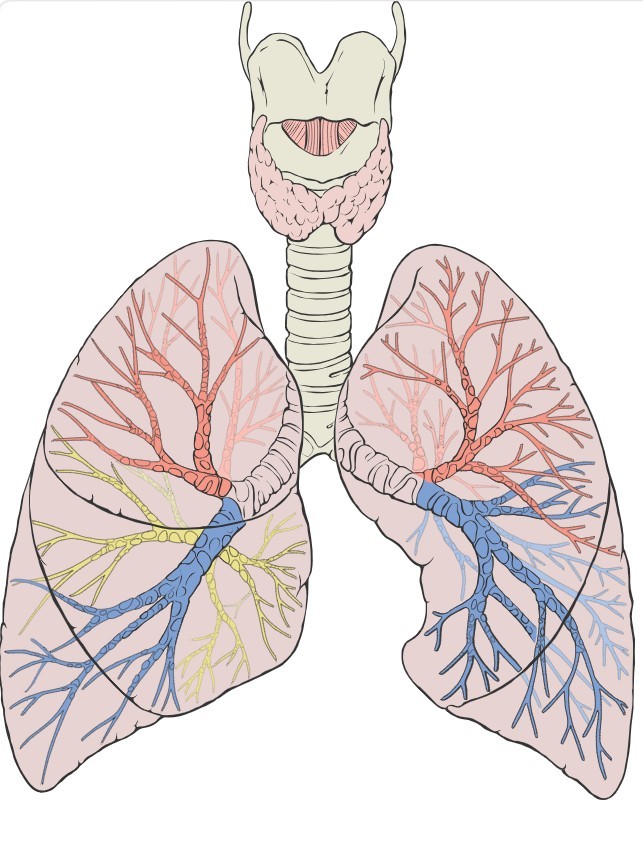

Gross anatomy

Lobes and fissures

2 fissures: oblique + horizontal

1 fissure: oblique only

Surface anatomy

The parietal pleura projects superiorly 1 inch (2.5 cm) above the midpoint of the medial third of the clavicle. Both pleural reflections cross the 8th rib at the mid-clavicular line, the 10th rib at the mid-axillary line, and reach the paraspinal region just below the 12th rib posteriorly. The lungs follow but extend two rib spaces less than the pleura below the 6th rib anteriorly.

The gap between lung margin and pleural reflection below the 6th rib anteriorly is the safe zone for thoracocentesis in the sitting patient. Intercostal drain insertion must respect these surface markings to avoid lung puncture.

Anatomical variations

- Horizontal fissure may be incomplete - partial or complete fusion of upper and middle lobes

- Superior segment of lower lobe may be delineated by a separate accessory fissure

- Accessory fissures and lobes may occur in one or both lungs

A normal variant of the apical segment of the right upper lobe - caused by failure of the azygos vein to migrate, creating a deep fissure invaginated by two layers of pleura. Not a true accessory lobe. Usually incidental on imaging but can cause technical difficulty during surgery.